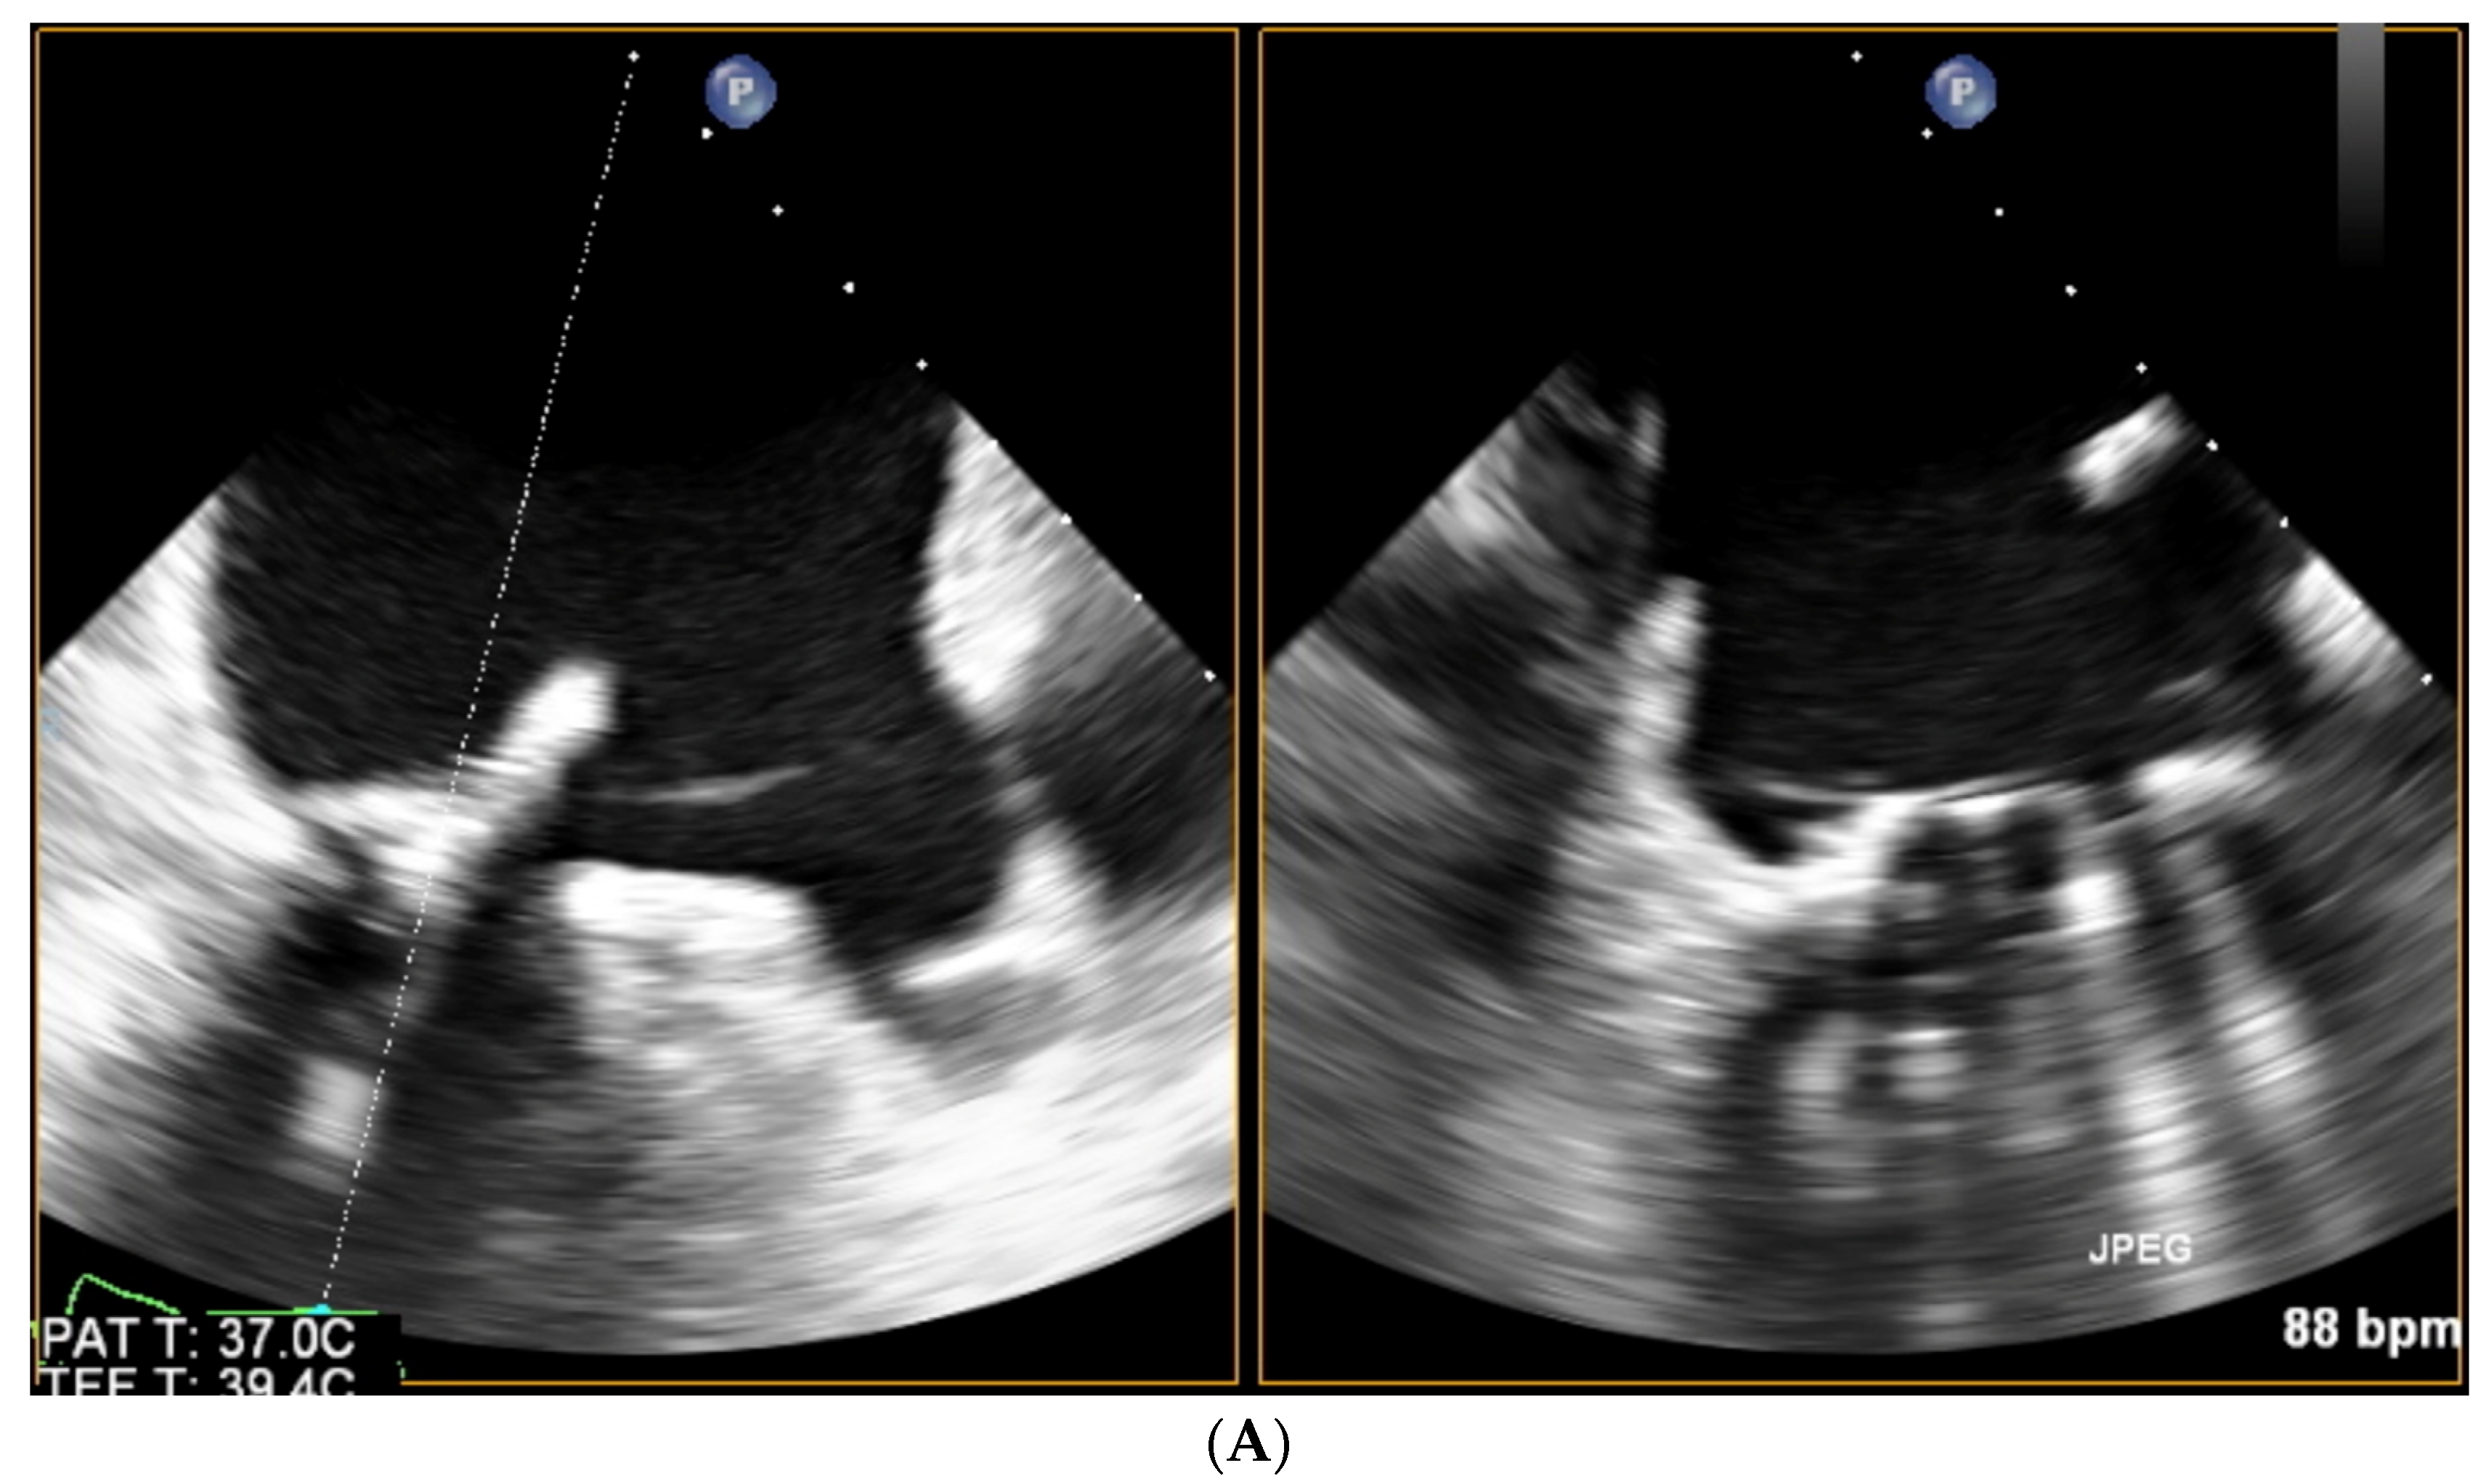

Paravalvular Leak Echo Imaging before and during the Percutaneous Procedure